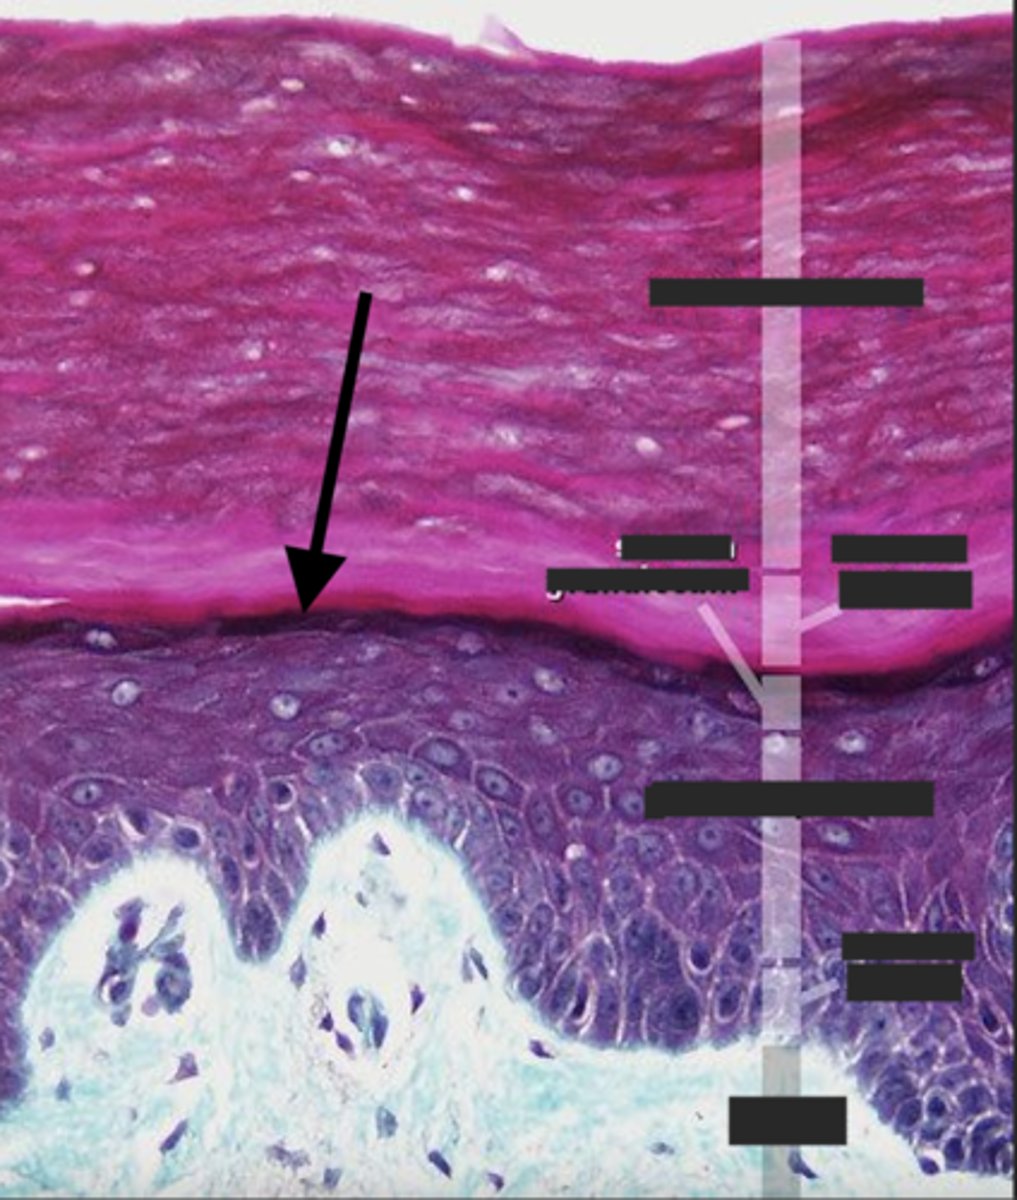

stratum corneum

What is the name of the layer indicated by A on the diagram?

stratum lucidum

What is the name of the layer indicated by B on the diagram?

stratum granulosum

What is the name of the layer indicated by C on the diagram?

stratum spinosum

What is the name of the layer indicated by D on the diagram?

stratum basale

What is the name of the layer indicated by E on the diagram?